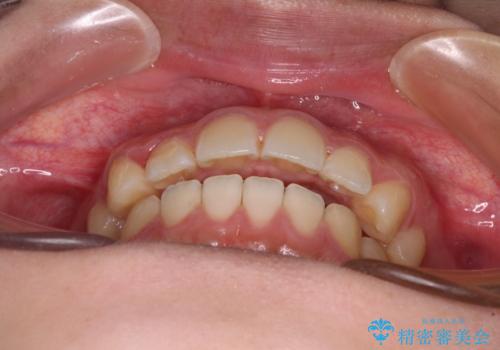

インビザライン単体で改善することも可能ですが、咬合力が強く、単位で達成する可能性が低いと考えられたため、カリエール・ディスタライザーという補助装置を併用して、より確実性を上げることとしました。

奥歯の咬み合わせを改善しながら、並行してインビザラインで歯列を整えることとしました。

カリエールディスタライザーを併用したことで、確実かつ短期間で治療を終えることができました。